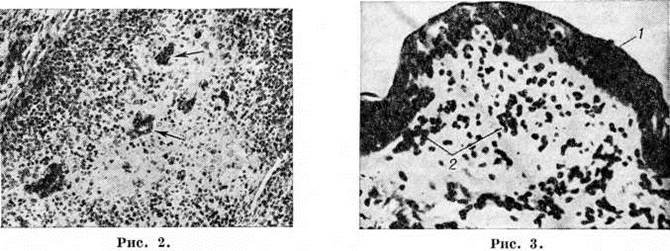

Рис. 2.

Микропрепарат ткани миндалины при кори: гиперплазия лимфоидного фолликула с образованием гигантских многоядерных клеток (указаны стрелками); × 230 Рис. 3. Микропрепарат кожи при кори: 1 — дистрофические изменения эпителия кожи; 2 — инфильтраты в дерме; × 350.

Сходные изменения отмечаются в других отделах лимфатических, системы — селезёнке, миндалинах (рисунок 2) и лимфоидной ткани. Многослойный плоский эпителий, покрывающий миндалины, а также слизистую оболочку щёк, мягкого и твёрдого неба, местами разрыхляется, в нем происходят дистрофические изменения, прежде всего вакуольная дистрофия (смотри полный свод знаний). В дальнейшем поверхностные слои эпителия слущиваются, а базальные слои инфильтрируются лимфоидными клетками и изредка нейтрофильными лейкоцитами. Отмечается также полнокровие стромы слизистой оболочки и подслизистой основы и небольшая, преимущественно лимфогистиоцитарная, их инфильтрация.

В коже выявляют очаговые дистрофические изменения эпителия, разрыхление эпителиального слоя и незначительную лимфолейкоцитарную его инфильтрацию; отмечаются полнокровие, отёк и лимфогистиоцитарная инфильтрация дермы, в основном тех её участков, которые прилегают к эпидермису (рисунок 3). Воспалительные инфильтраты располагаются преимущественно вокруг сосудов и в меньшей мере вокруг выводных протоков сальных и потовых желёз. Иногда наблюдается образование гигантских клеток. Вблизи этих участков происходит ускоренное и неправильное ороговение кожи — паракератоз (смотри полный свод знаний). В дальнейшем происходит слущивание поражённого эпителия.